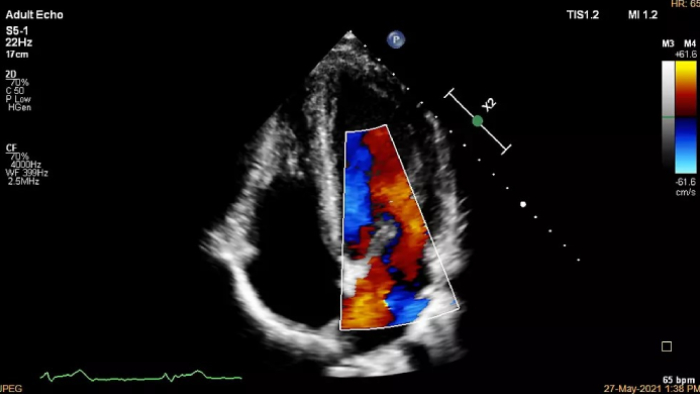

If you were registered for ESC 2023, but were not able to attend the satellite symposium, you can still view it through the ESC website. Top cardiology thought leaders addressed some of the major challenges in peri-interventional and diagnostic echocardiography, such as advancing and complementing imaging techniques during tricuspid valve interventions, a revolutionary imaging workflow for occlusion of the left atrial appendage, and the importance of first-time-right ultrasound imaging during cancer therapy.

You can still access recordings of 4 full days of hands-on workshops about best practices in multimodality cardiac imaging with expert teams. See first-time-right imaging for cardiac care, including valvular and related diseases, cardiomyopathies, and intracardiac masses and cardiac tumors.